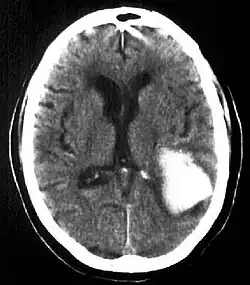

| Multiple intraparenchymal hemorrhage | |

Intraparenchymal hemorrhage is one form of intracerebral bleeding in which there is bleeding within brain parenchyma. The other form is intraventricular hemorrhage).[1]

Intraparenchymal hemorrhage accounts for approximately 8-13% of all strokes and results from a wide spectrum of disorders. It is more likely to result in death or major disability than ischemic stroke or subarachnoid hemorrhage, and therefore constitutes an immediate medical emergency. Intracerebral hemorrhages and accompanying edema may disrupt or compress adjacent brain tissue, leading to neurological dysfunction. Substantial displacement of brain parenchyma may cause elevation of intracranial pressure (ICP) and potentially fatal herniation syndromes.

Diagnosis

Computed tomography (CT scan): A CT scan may be normal if it is done soon after the onset of symptoms. A CT scan is the best test to look for bleeding in or around your brain. In some hospitals, a perfusion CT scan may be done to see where the blood is flowing and not flowing in your brain.